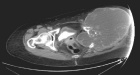

53 year old female with pelvic pain and fevers

History of left hip disarticulation due to a 2005 motor vehicle accident